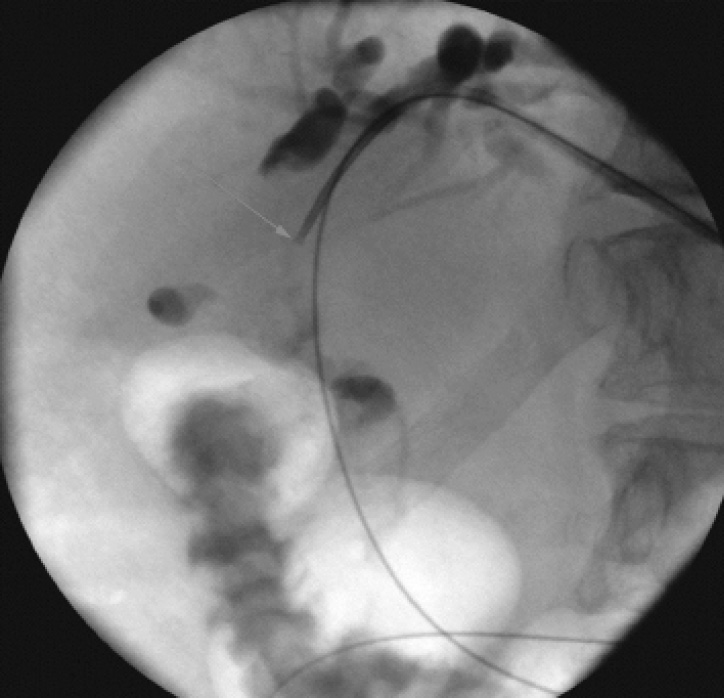

Заключение гистологического исследования: на фоне муцина гландулярный эпителий протокового типа и пласты деформированных атипичных клеток аденогенной карциномы. Принято решение о выполнении фотодинамической терапии. В плановом порядке в январе 2020 г. больной проведена чрескожная чреспеченочная эндобилиарная фотодинамическая терапия холангиокарциномы гепатикохоледоха (рис. 3, 4).

Рис. 3. Чрескожная чреспеченочная эндобилиарная фотодинамическая терапия холангиокарциномы. Стрелкой указан кончик микрокатетера (начало процедуры)